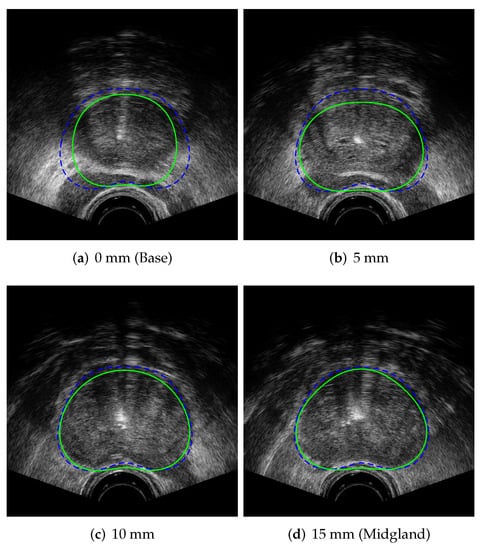

where the corresponds to the graph-cut procedure, and the optimization is carried out through a pattern search algorithm. Once the optimal centre point has been found, with a minimal labelling cost across all of the slices, the prostate segmentation is complete, as shown in Figure 10. All regions labelled with after graph cutting are inside of the prostate, which could be represented in a binary image where all of the pixels inside of the regions have a value of one and all other pixels are zero. To smooth out the segmented prostate contour, the contour model is fit to the pixels on the perimeter of the binary region . The perimeter pixels are transformed to the contour model coordinate system using (50), and then the model is fit to these pixel points from the least-squares fitting given in (6), thus creating a 3D contour model for the segmented prostate; see Figure 11. The results of the segmentation on a number of patient image sets is given in Section 6.

Figure 11.

Segmented prostate contours in TRUS image slice from our proposed algorithm, , shown as solid green line and compared with input clinician-segmented contour, , indicated with dashed blue line.

where is the output contour of our proposed prostate segmentation algorithm, for a particular TRUS image set, and is the clinician-segmented contour for the same image set. Figure 15 shows the average Jaccard index score values with respect to the z-axis depth of the TRUS image, where the first image slice at a depth of 0 mm corresponds to the base of the prostate, the midgland of the prostate is located at 15 mm, and the apex of the prostate is at a depth of 30 mm, as indicated in Figure 11.

The average Jaccard index values across all images slices are slightly lower than those reported for clinicians [42], indicating that some additional work to increase contouring accuracy may be required. The per-slice Jaccard index values presented in Figure 15 indicate that the contouring has roughly the same contouring performance across all prostate image slices, with the exceptions of the base image slice (0 mm), which has slightly lower than average accuracy, and the apex image slice (30 mm), which has higher than average accuracy. These per-slice results compare favourably with the variances reported in [42], with the base slice segmentation variance being higher for both the algorithm and between clinicians. The accuracy of the prostate midgland contouring is the primary area where the algorithm performs slightly worse than clinicians [42] and indicates the primary area where the algorithm accuracy can be improved.